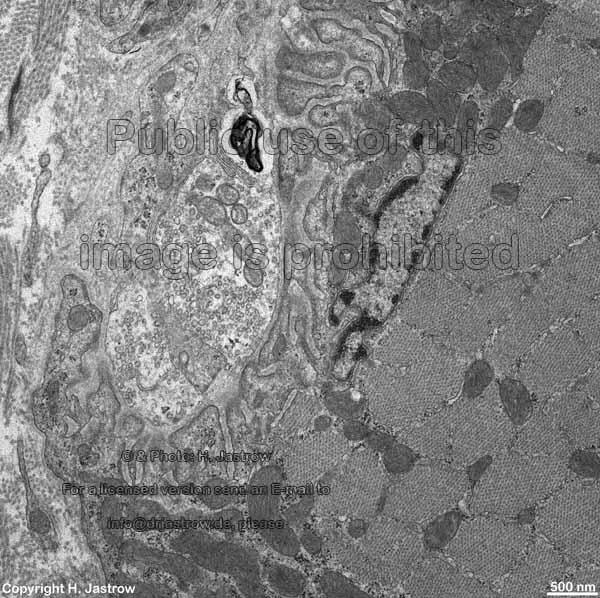

Miniaturbildübersicht neuromuskuläre Endplatte (Synapsis neuromuscularis):

motorische Endplatte B

Übersicht (Zunge, Ratte)

Detail B1: eigentliche moto-

rische Endplatte B

mot. Endplatte B

Detail B2

Eine neuromuskuläre oder motorische Endplatte = myoneurale Synapse (Terminologia histologica: Synapsis neuromuscularis, englisch: motor endplate, neuromuscular junction oder myoneural junction) stellt die Endigung einer somatomotorischen Nervenfaser zur Skelettmuskulatur dar und dient der Steuerung (Innervation) der Muskulatur. Es handelt sich also um eine spezialisierte chemische Synapse, deren flachovale, zur Muskulatur hingewandte Oberfläche ca. 4 bis zu maximal 40 µm im Durchmesser groß ist. Kommen Aktionspotentiale über das zuleitende Axon in dessen plattenartige Endauftreibung, so öffnen sich spannungsabhängige Kalziumionenkanäle. Durch den Kalziumioneneinstrom findet dann in weniger als 1 Millisekunde an der präsynaptischen Zellmembran die Exozytose acyethylcholinhaltiger Neurotransmittervesikel statt. Genauer gesagt, verschmelzen kleine Anteile der Transmittervesikelmembran mit der präsynaptischen Membran und dabei diffundiert Acytylcholin in den darunterliegenden, 20 bis 50 nm weiten, synaptischen Spalt, während gespaltener Neurotransmitter (Acetyl und Cholin) aufgenommen wird, bevor sich die Bläschenmembran durch die Anlagerung von Clathrinmolekülen wieder schließt und ins Innere des Endkolbens zurückwandert (genauere Beschreibung siehe bei Synapse). Das freigesetzte Acethylcholin bindet an die Acethylcholinrezeptoren (ca. 10.000 pro 1 µm²) der elektronendichteren post- (= sub)synaptischen Zellmembran (Plasmalemm der Muskelfaser = Sarkolemm). Dies führt zur Öffnung der Ionenkanäle der Acethylcholinrezeptoren, die durch die Zellmembran reichende Tunnelproteine sind. Dadurch kommt es zu einem extrem schnellen Natriumeinstrom und Kaliumausstrom, wobei der Natriumioneneinwärtsstrom überwiegt, was zu einer Erregung der Muskelzelle führt, wodurch sich spannungsabhängige Kalziumionenkanäle öffnen, Kalziumionen einströmen und letztlich eine Muskelkontraktion zustandekommt. Acetylcholin wird nur für 0,5 Millisekunden an seine Rezeptoren in der subsynaptischen Membran gebunden, danach wird es durch das ebenfalls an dieser Membran verankerte Enzym Acetylcholinesterase in Acetyl und Cholin gespalten. Die Spaltprodukte diffundieren in den synaptischen Spaltraum und werden, wie oben beschrieben, wieder in den synaptischen Endkolben aufgenommen.

Typischerweise finden sich in in präsynaptischen Endkolben viele kleine Mitochondrien vom Crista-Typ und bis zu 1.000.000 Neurotransmittervesikel mit durchschnittlichen Durchmessern von 50 nm, die jeweils 1.000 bis 10.000 Achetylcholin Moleküle enthalten. Zahlreiche Neurofilamente und einige Neurotubuli reichen nur ein Stück weit in die Endplatte hinein. Die der Muskulatur abgewandte Seite des Endkolbens wird von Ausläufern von Schwannschen Scheidenzellen bedeckt und damit isoliert. Der gesamte Endkolben beult sich ein Stück weit in das darunterliegende Sarkolemm ein, welches viele bis über 1 µm tiefe, parallele Falten aufweist, weshalb man von einem subneuralen Faltenfeld spricht (in den hier gezeigten Abbildungen ist dies nicht zu erkennen). Die Falten können sich auch nochmals (sekundär) verzweigen, wodurch eine enorme Oberflächenvergrößerung erfolgt. Im nur wenige Nanometer weiten Lumen der Falten findet sich glykoproteinreiches, elektronendichteres Material, welches eine Fortsetzung der Basalmembran der Muskelfaser darstellt. Typischerweise teilt sich ein somatomotorisches Axon vor seinem Ende in viele Kollateralen, die alle als motorische Endplatten enden. Da diese alle gemeinsam erregt werden, sobald ein Aktionspotential im Axon ankommt, werden sie als funktionelle (motorische) Einheit zusammengefaßt. Die Größe einer motorischen Einheit entscheidet, wieviele Skelettmuskelfasern sich gleichzeitig zusammenziehen (kontrahieren). Je differenziertere Bewegungen ein Muskel ausführt, desto kleiner sind die hier anzutreffenden motorischen Einheiten. In der Nähe der postsynaptischen Membranen finden sich in den innervierten Muskelzellen häufig beta-Glykogenkörnchen, kleine Mitochondrien vom Crista-Typ und Zellkerne. Muskelfilamente kommen erst in einiger Entfernung davon vor.